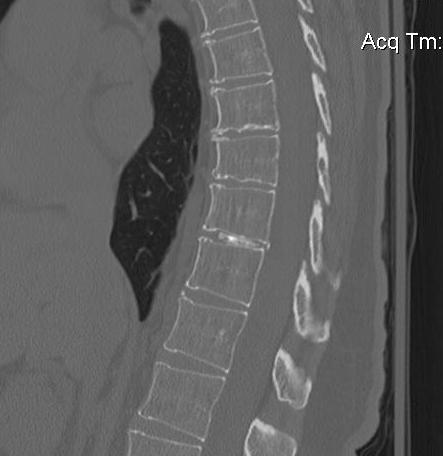

Xray

Disc space narrowing / degenerative changes

> 50% thoracic discs associated with calcified disc material in canal

- probably indicates chronicity

MRI

Very sensitive

- 40% incidence asymptomatic thoracic disc protrusion